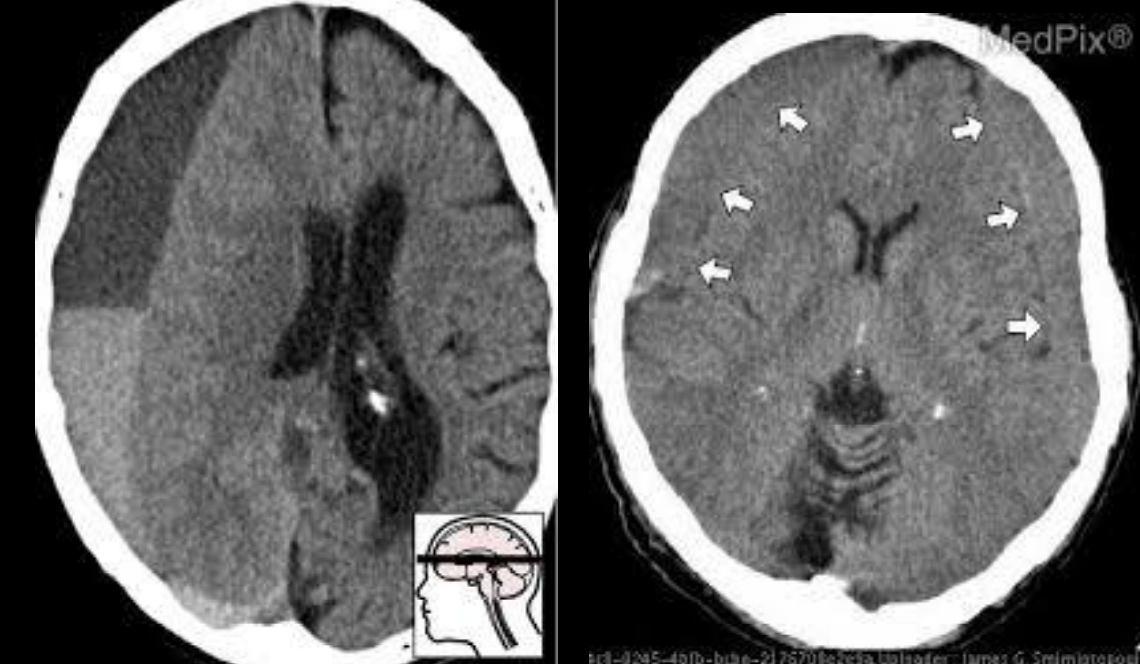

Hematoma subdural en TC

A

Colección semilunar / cóncava adyacente a superficie cerebral

venoso, lento

10

Q

Hematoma epidural en TC

Colección biconvexa/lenticular, NO cruza suturas

arterial

11

Arteria afectada en el hematoma epidural

A. Meníngea media

12

Epidural: hallazgo asociado casi siempre

• Fractura

• Herniación/efecto masa